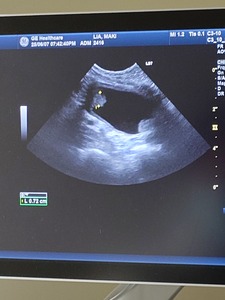

なので整形専門医のいる病院へ

レントゲンでは異常は見つからず

触診でも、いつもスーンな表情だったらしく

原因わからず。